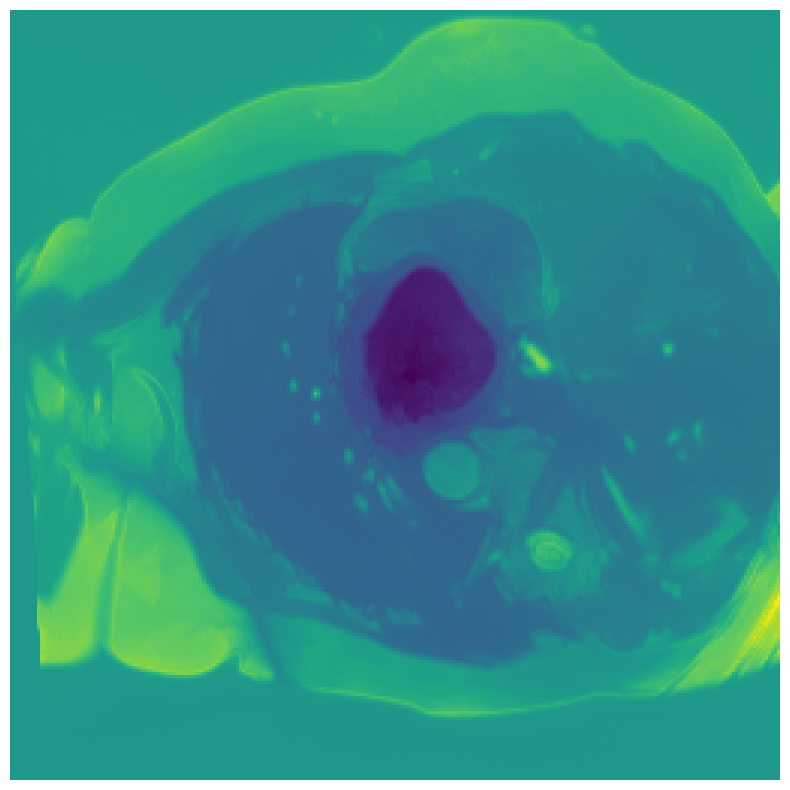

We normalize the volumes and resize the slices to pixels. As the official dataset comes with full annotations, we create a synthetic point ground truth. This is done by first randomly choosing the centers of the point annotations within the class masks, followed by filling an ellipse with axes lengths of and (in pixels) around each center. The intersections of these elliptic discs with the underlying full annotations are then used as our point ground truth. See Figure 2 for an example of the created weak annotation mask. The point annotations are created for every slice, one for each foreground object present in the slice.

5.1 Segmentation of cardiac structures

The average 3D Dice scores and HD95 values on the ACDC test set are given in Table 2, and boxplots in figures 4 and 5 show the distributions. We see that, in terms of DSC, the proposed strategy of using intensity-aware distances withing boundary loss performs better than simply using the Euclidean distance, with the best results achieved by using the strictly intensity based MBD. The HD95 however favors the original version of , which may be do to its smoother predictions and less fragmentation and oversegmentation. The CRF-loss results are significantly worse in both metrics.

In Figure 3 we show the 3D DSC validation curve evolution for a single run. The CRF-loss seems to have converged to a low DSC value, while all settings combining CE and boundary loss reach values close to the full supervision in the beginning of the training and then slowly collapse towards to the point annotations. The MBD version stands out, degrading slower, thus providing a wider range of potentially good models for evaluation.

Qualitative comparison

In Figure 6 we provide qualitative results on a number of randomly chosen test set slices. Upon visual inspection, we can observe that training with the intensity-aware distances (particularly with and ) follows the image gradients better and is better at recovering the underlying shape than the Euclidean version. The CRF-loss seems to recover the shape of the myocardium and left ventricle to some extent, but fails entirely on the right ventricle.